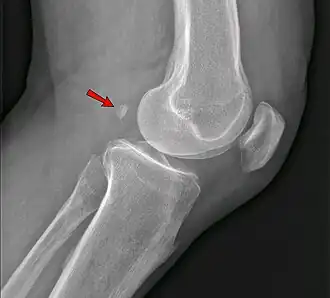

Knee